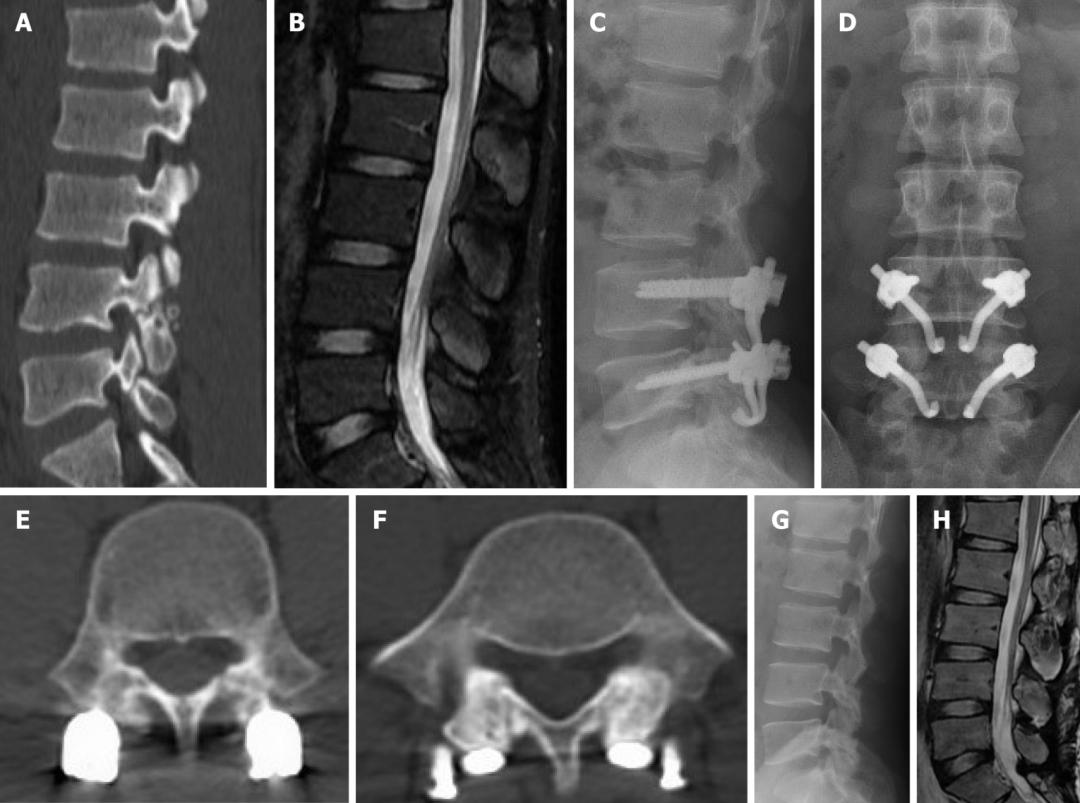

L5椎弓峡部裂典型病例一:男,32岁。A,B: 腰椎正位侧位X线片示无明显椎弓峡部裂征象; C: 腰椎 MRI正中矢状面T1WI示L5棘突基底部与硬膜之间出现脂肪高信号带(箭头示); D: 腰椎CT矢状面重建示L5椎弓峡部骨质不连(箭头示)。

L5椎弓峡部裂典型病例二:男,35岁。A,B: 腰椎正位侧位X线片均无明显椎弓峡部裂征象; C: 腰椎MRI正中矢状面T1WI示L5棘突基底部与硬膜之间出现脂肪高信号带(箭头示); D: 腰椎CT矢状面重建示L5椎弓峡部骨质不连,裂隙较细(箭头示)。

腰椎MRI正中矢状面 T1WI。A:棘突基底部和硬膜之间未见脂肪沉积;B:L5棘突基底部与硬膜之间可见线状脂肪高信号带(箭头示)

在峡部裂继发的椎体滑脱患者中MRI正中矢状面TIWI示棘突基底部与硬膜之间会出现脂肪的异常增多沉积,且椎体滑脱越严重脂肪增多也越明显。 而在尚未出现椎体滑脱的隐匿性峡部裂患者中是否也存在上述脂肪增多的影像学表现呢?最近,一项回顾性研究发现棘突基底部与硬膜之间的脂肪沉积征对隐匿性腰椎峡部裂的诊断有一定的特异性,有助于早期诊断峡部裂。

棘突基底部与硬膜之间线状的脂肪沉积对于隐匿性峡部裂的诊断有一定的特异性,在常规腰椎MRI上可进行简单观察,并作为峡部骨质信号不连续的有效补充,也可作为寻求 CT螺旋扫描及多平重建以明确诊断的有用提示。